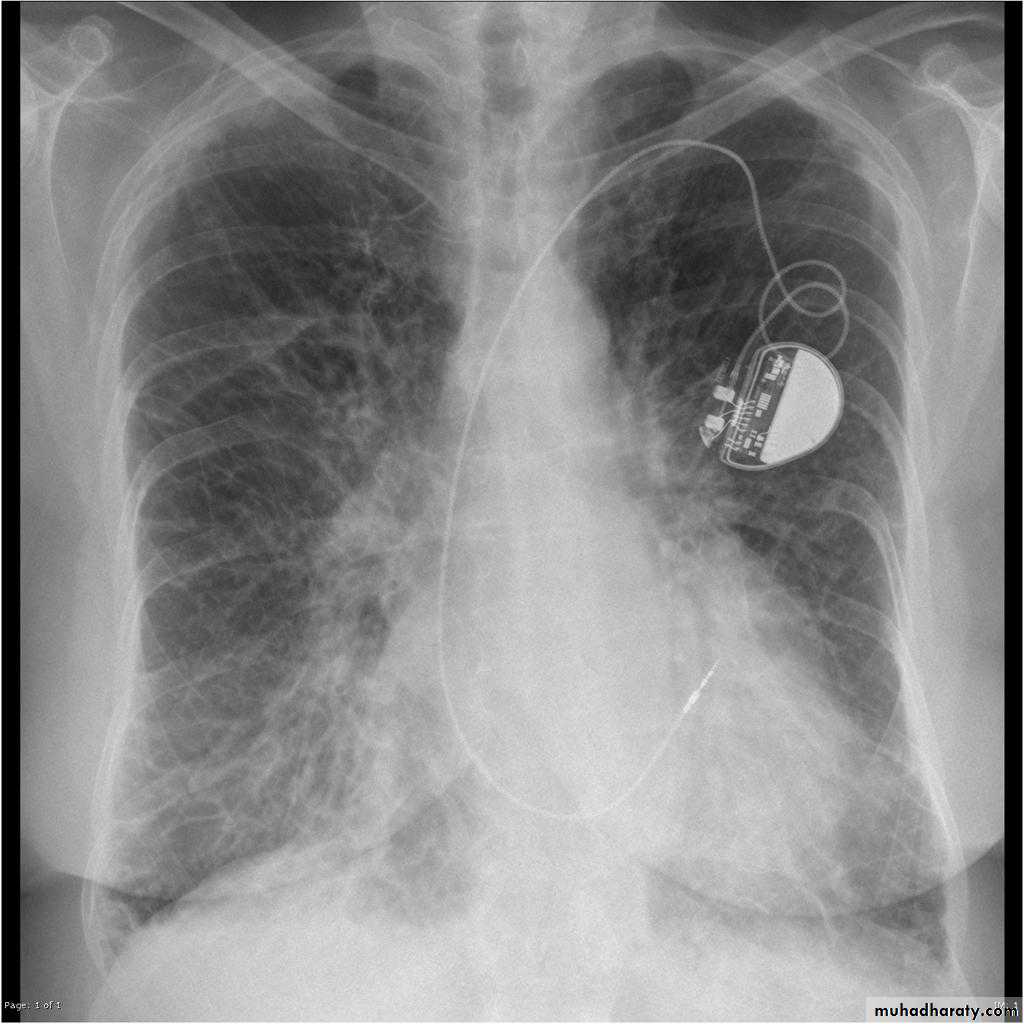

Heart Assessment & measurement

The heart has a somewhat conical form and is enclosed by pericardium. It is positioned posteriorly to the body of the sternum with one-third of it is situated on the right and two-thirds on the left of the midline .

Cardiothoracic ratio (CTR) = Cardiac Width : Thoracic Width

A CTR of greater than 1:2 (50%) is considered abnormal. This however, assumes the projection is Posterior-Anterior (PA), and that cardiac size is not exaggerated by factors such as patient rotation or an incomplete breath in .

The cardiothoracic ratio aids in the detection of cardiomegaly, or more broadly,enlargement of the cardiac silhouette. .

Enlargement of the cardiac silhouette on chest x-ray can be due to a number of causes :

cardiomegaly (most common cause by far)pericardial effusion